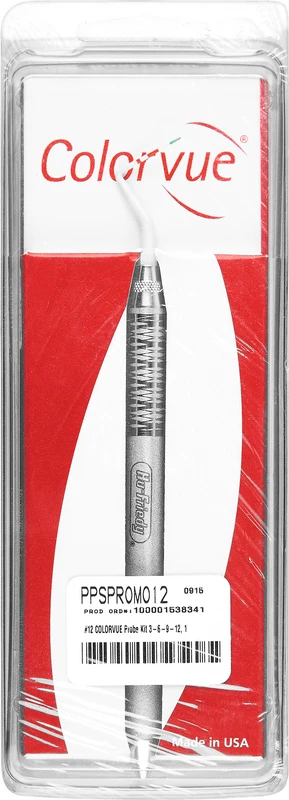

Die Colorvue Sonde PerioScreen fra Hu-Friedy muliggjør rask og enkel bestemmelse av periodontale lommedybder før endelig undersøkelse. En lett forståelig fargekoding med fargene grønn og rød viser om periodontitt er til stede eller ikke.

| Weight | 0,048 kg |

|---|---|

| Variant | <b>Introduksjonssett</b> spiss (markering 3-6-9-12), 1 håndtak |